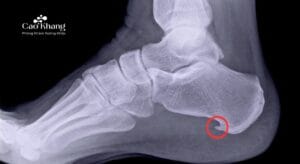

Gai gót chân là tình trạng hình thành gai xương nhỏ ở mặt dưới xương gót, thường gặp nhất ở những người trung niên, người hay đi lại nhiều hoặc thừa cân. Nguyên nhân chủ yếu là do quá trình viêm, tổn thương kéo dài của cân gan bàn chân – lớp mô dày nối từ gót đến các ngón chân, đóng vai trò như một “dây đàn” giúp nâng đỡ vòm bàn chân.

Khi chịu áp lực lớn trong thời gian dài (đi bộ nhiều, đứng lâu, tăng cân…), cân gan bàn chân bị kéo căng, viêm mạn tính và dần dần hình thành một gai xương nhỏ tại điểm bám vào xương gót. Gai xương này không tự gây đau, nhưng vùng viêm quanh gai lại vô cùng nhạy cảm. Đặc biệt, mỗi khi đi bộ hoặc đứng lâu, vùng gót phải chịu toàn bộ trọng lượng cơ thể, làm cơn đau tăng rõ rệt, nhất là lúc mới bước xuống giường vào buổi sáng.